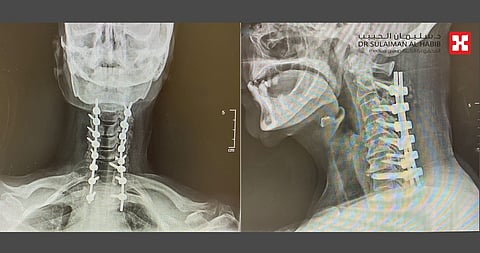

وفي النهاية خلص الفريق الطبي إلى خطة علاجية، وأجرى للمريضة عملية تم فيها تحرير العمود الفقري من الضغط بإزالة الانزلاق الغضروفي وتثبيت الفقرة الرقبية رقم "2" وتوصيلها مع الفقرات الصدرية، تحت جهاز المراقبة العصبية.

واستمرت العملية لنحو 3 ساعات ومضت بسلاسة وانتهت ولله الحمد بالنجاح التام، ونُقلت المريضة من غرفة العمليات إلى غرفة التنويم، حيث أمضت 5 أيام، تحسنت حالتها خلالها مع الرعاية الطبية الحثيثة، كما أنها استعادت قدرتها على المشي بعد نحو 36 ساعة من العملية.